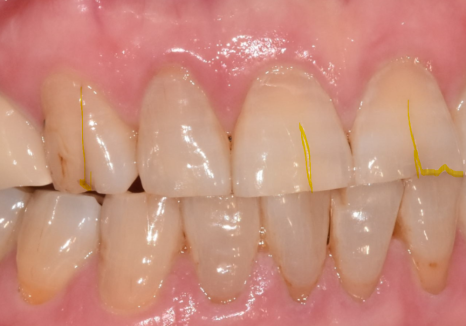

뿌리만 남은 앞니는 우선 발치를 진행했는데,

다행히 CT 상 잇몸뼈가 아주 튼튼한 상태였어요.

덕분에 번거로운 뼈이식 과정 없이

그날 바로 임플란트를 심어드리는

즉시 식립이 가능했습니다.

그렇게 두 달 정도 시간이 흘러

임플란트와 뼈가 단단하게 잘 붙은 것을 확인하고,

이제 그 위에 올릴 치아머리를

만들 차례가 되었습니다.

여기서 가장 공을 들여야 할 부분은 무엇일까요?

바로 기존에 먼저 해두었던

다른 앞니 보철물들과

색상을 감쪽같이 맞추는 일입니다.

위의 사진처럼 새로 만든 치아가

유독 하얗게 둥둥 떠 보인다면

아무리 튼튼하게 잘 심었어도

성공적인 치료라고 말하기는 어렵겠죠.

주변 치아들과 마치 원래부터 하나였던 것처럼

자연스럽게 어우러지도록 만드는 데

가장 많은 정성을 쏟았습니다.

드디어 완성된 모습입니다.

어떤 게 임플란트인지 한눈에 찾기 어려우시죠?

241101

색상은 물론이고 모양까지

주변 치아와 참 잘 어우러져서

환자분도 저도 무척 만족스러웠던 사례였습니다.^^